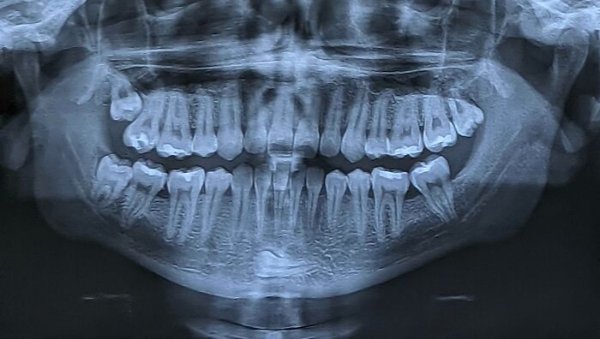

Fascinating Medical Photos